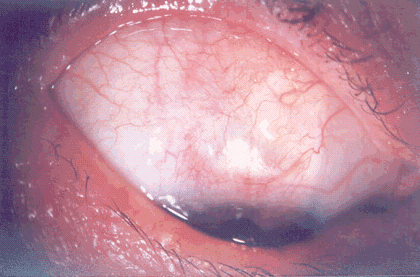

У всех пациентов 1-ой группы фильтрационная подушка была выражена хорошо, кистозных изменений не наблюдалось. В отдаленном послеоперационном периоде отмечалось некоторое уплощение фильтрационной подушки (рис. 3).

Рис. 3. Фильтрационная подушка через 3 мес. после реоперации